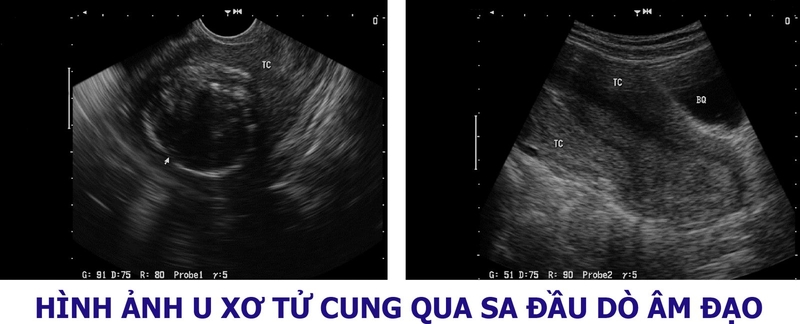

Siêu âm tử cung là loại hình siêu âm đặc biệt so với các hình thức siêu âm thông thường hiện nay. Có 3 loại siêu âm có thể giúp chẩn đoán u xơ tử cung là: Siêu âm đường bụng, siêu âm bơm nước buồng trứng và siêu âm đầu dò âm đạo.

Siêu âm bơm nước tử cungViệc siêu âm tử cung có thể phát hiện ra những nguyên nhân của triệu chứng như chảy máu tử cung, sảy thai nhiều lần, vô sinh. Từ đó giúp chẩn đoán u xơ tử cung ở những vị trí nào, cấu trúc và kích thước bao nhiêu. Chẩn đoán phân biệt u xơ tử cung và các bệnh lý khác ở vùng chậu như: Bệnh liên quan trực tràng, bàng quang.

U xơ tử cung khi siêu âm hoàn toàn có khả năng phát hiện bệnh, không những vậy, quá trình siêu âm còn giúp bác sĩ xác định được vị trí, tình trạng và mức độ nguy hiểm của khối u. Vì thế ngay khi gặp các biểu hiện u xơ tử cung bạn cần siêu âm để chẩn đoán chính xác về tình trạng bản thân nhé.